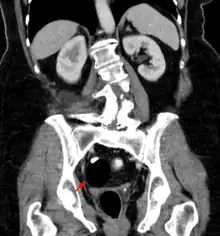

Diagnosis

Teratomas are thought to originate in utero, so can be considered congenital tumors. Many teratomas are not diagnosed until much later in childhood or in adulthood. Large tumors are more likely to be diagnosed early on. Sacrococcygeal and cervical teratomas are often detected by prenatal ultrasound. Additional diagnostic methods may include prenatal magnetic resonance imaging. In rare circumstances, the tumor is so large that the fetus may be damaged or die. In the case of large sacrococcygeal teratomas, a significant portion of the fetus' blood flow is redirected toward the teratoma (a phenomenon called steal syndrome), causing heart failure, or hydrops, of the fetus. In certain cases, fetal surgery may be indicated.

Beyond the newborn period, symptoms of a teratoma depend on its location and organ of origin. Ovarian teratomas often present with abdominal or pelvic pain, caused by torsion of the ovary or irritation of its ligaments. A recently discovered condition where ovarian teratomas cause encephalitis associated with antibodies against the N-methyl-D-aspartate receptor antibody (NMDAR) - often referred to as "anti-NMDA receptor encephalitis", was identified as a serious complication. Patients develop a multistage illness that progresses from psychosis, memory deficits, seizures, and language disintegration into a state of unresponsiveness with catatonic features often associated with abnormal movements, and autonomic and breathing instability.[34] Testicular teratomas present as a palpable mass in the testis; mediastinal teratomas often cause compression of the lungs or the airways and may present with chest pain and/or respiratory symptoms.